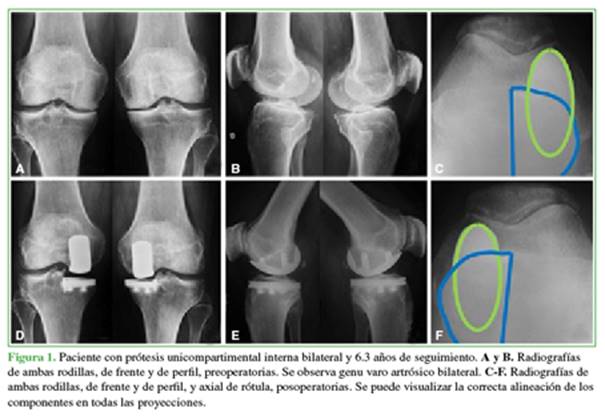

Antes de la cirugía, se tomaron radiografías de ambas rodillas, de frente y de perfil con carga bipodálica, axial de rótula a 30º de flexión (Merchant), de frente en semiflexión de 45º (Schuss), y radiografías en varo y valgo forzado para evaluar la suficiencia de los ligamentos colaterales, la corrección del deseje y el pinzamiento del compartimento contralateral. En el posoperatorio, se tomaron radiografías de frente, de perfil y axial de rótula (Figura 1).

Se midió el eje femorotibial pre- y posoperatorio con un goniómetro. Se cuantificó el grado de artrosis en el compartimento afectado según las clasificaciones de Ahlback para genu varo, y de Kellgren-Lawrence para genu valgo. Las evaluaciones estuvieron a cargo de uno de los autores que no participó en la cirugía.

En las radiografías, 81 rodillas presentaban genu varo artrósico, el 9,9% (n = 8) correspondía al grado 3 de la clasificación de Ahlback; el 43,2% (n = 35), al grado 4 y el 46,9% (n = 38), al grado 5. De estos últimos, 22 (57,9%) tenían subluxación en el plano coronal reductible en las radiografías con valgo forzado. En todos los casos de genu valgo artrósico, se constató un grado 4 de degeneración según la clasificación de Kellgren-Lawrence. El eje femo-rotibial preoperatorio fue de 9° ± 2,3° de varo para genu varo artrósico (rango 4-15) y de 14,6° ± 4,2° de valgo para genu valgo artrósico (rango 10-20). El eje femorotibial posoperatorio se corrigió a 3,6° ± 1,4° de varo (rango 1-9) y 7,4° ± 2,8° de valgo (rango 4-10), respectivamente (p <0,05) (Tabla 2, Figura 4).